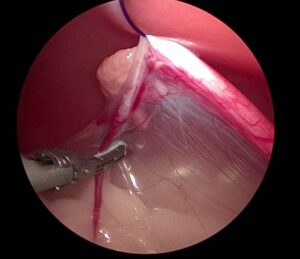

卵巣動静脈をシーリングデバイスで止血・切離